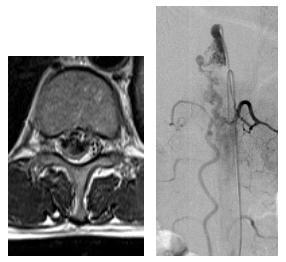

脊髄で出血する病気の多くは、「脊髄動静脈奇形」や「脊髄海綿状血管腫」とよばれる、脊髄の血管に先天的あるいは後天的に異常をきたし、脆い部分から出血することが多いです。特に脊髄動静脈奇形はさまざまなバリエーションがあり、それぞれ出血しやすいタイプや、脊髄の循環障害を起こして進行性に麻痺や感覚障害、排尿排便障害をきたすタイプもあります。

一般的には「脊髄髄内動静脈奇形」は先天的な要素が大きいため、若年発症が多く、血管内治療や放射線治療、直達手術を組み合わせて治療を行うことが多いです。

「傍脊髄動静脈奇形、傍脊髄動静脈瘻」と呼ばれるものは、先天的要素と後天的要素が組み合わさっていることが多く、こちらもその異常血管の形態に応じて血管内治療と直達手術を組み合わせて治療を行います。

「脊髄硬膜動静脈瘻、硬膜外動静脈瘻」とよばれるタイプは、後天的な要素が大きく、比較的血管構築が単純なものが多いのですが、正常の脊髄血管との関係によって、血管内治療と直達手術を選択することが多いです。

その他、さまざまなタイプがありますが、全体的に発生頻度は低いため、脊椎脊髄専門医でもこの疾患に精通した専門医も少ないのが現状です。正しい診断とそれに対する適切な治療が行われないと、症状が悪化したり、その後の治療がさらに困難になってしまう場合があります。基本的には脳血管障害と同じく、直達手術、カテーテルを用いた血管内治療、放射線治療を組み合わせて行うため、脳神経外科にて診断治療を行うことが一般的です。本院ではさまざまな検査方法を駆使して正確に診断し、ハイブリッド手術室にて脳神経血管内治療と直達手術を組み合わた精密な治療を行っています。